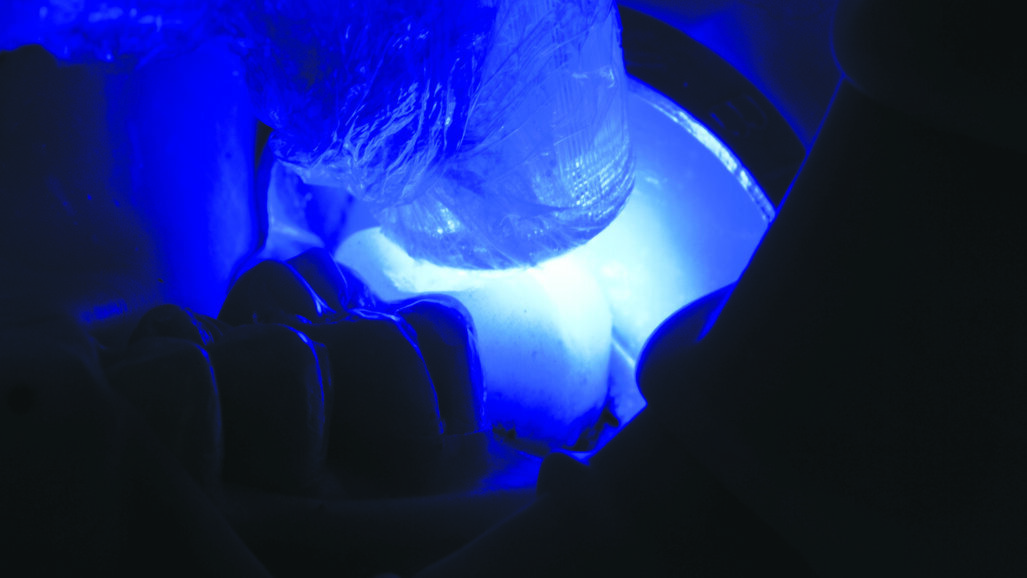

Fig. 12: Tack cure for 1-2 seconds.(!) Tip: Do not exceed recommended tack cure time, otherwise clean-up will be difficult. For a controlled time, use 3M™ Elipar™ S10 LED Curing Light or 3M™ Elipar™ DeepCure-S LED Curing Light tack curing function.